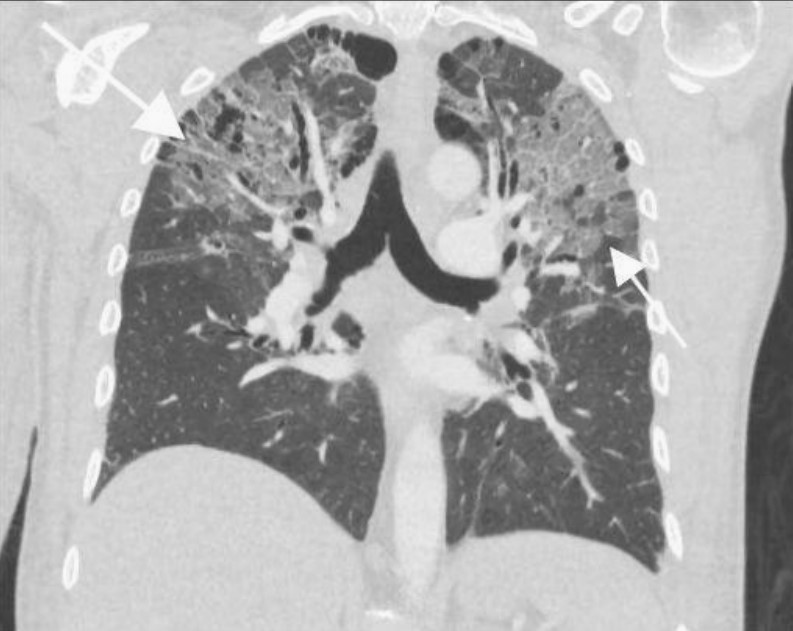

患者左下肢X線片顯示腓骨和脛骨骨折。胸片顯示上肺葉雙側肺泡混濁,這些不明確的斑片狀氣腔模糊是非特異性的,可見于肺水腫、誤吸或感染。繼續(xù)為患者行胸部CT檢查,CT顯示肺動脈干、左或右肺動脈主干或肺葉動脈無充盈缺損,雙側胸腔積液。肺窗顯示雙側上、左中肺野斑片狀磨玻璃影伴小葉間隔增厚。

鑒于患者的骨折和呼吸困難,考慮肺脂肪栓塞。與肺脂肪栓塞相關的最常見CT結果包括局灶性或彌漫性磨玻璃影、片狀或彌漫性實變區(qū)以及各種小結節(jié)(<10 mm)。罕見觀察到肺動脈內(nèi)脂肪衰減充盈缺損?;颊咦罱K診斷為肺脂肪栓塞。

圖2 冠狀位CT顯示位于雙上肺野和左中肺野的斑片狀磨玻璃影伴小葉間隔增厚(白色箭頭)